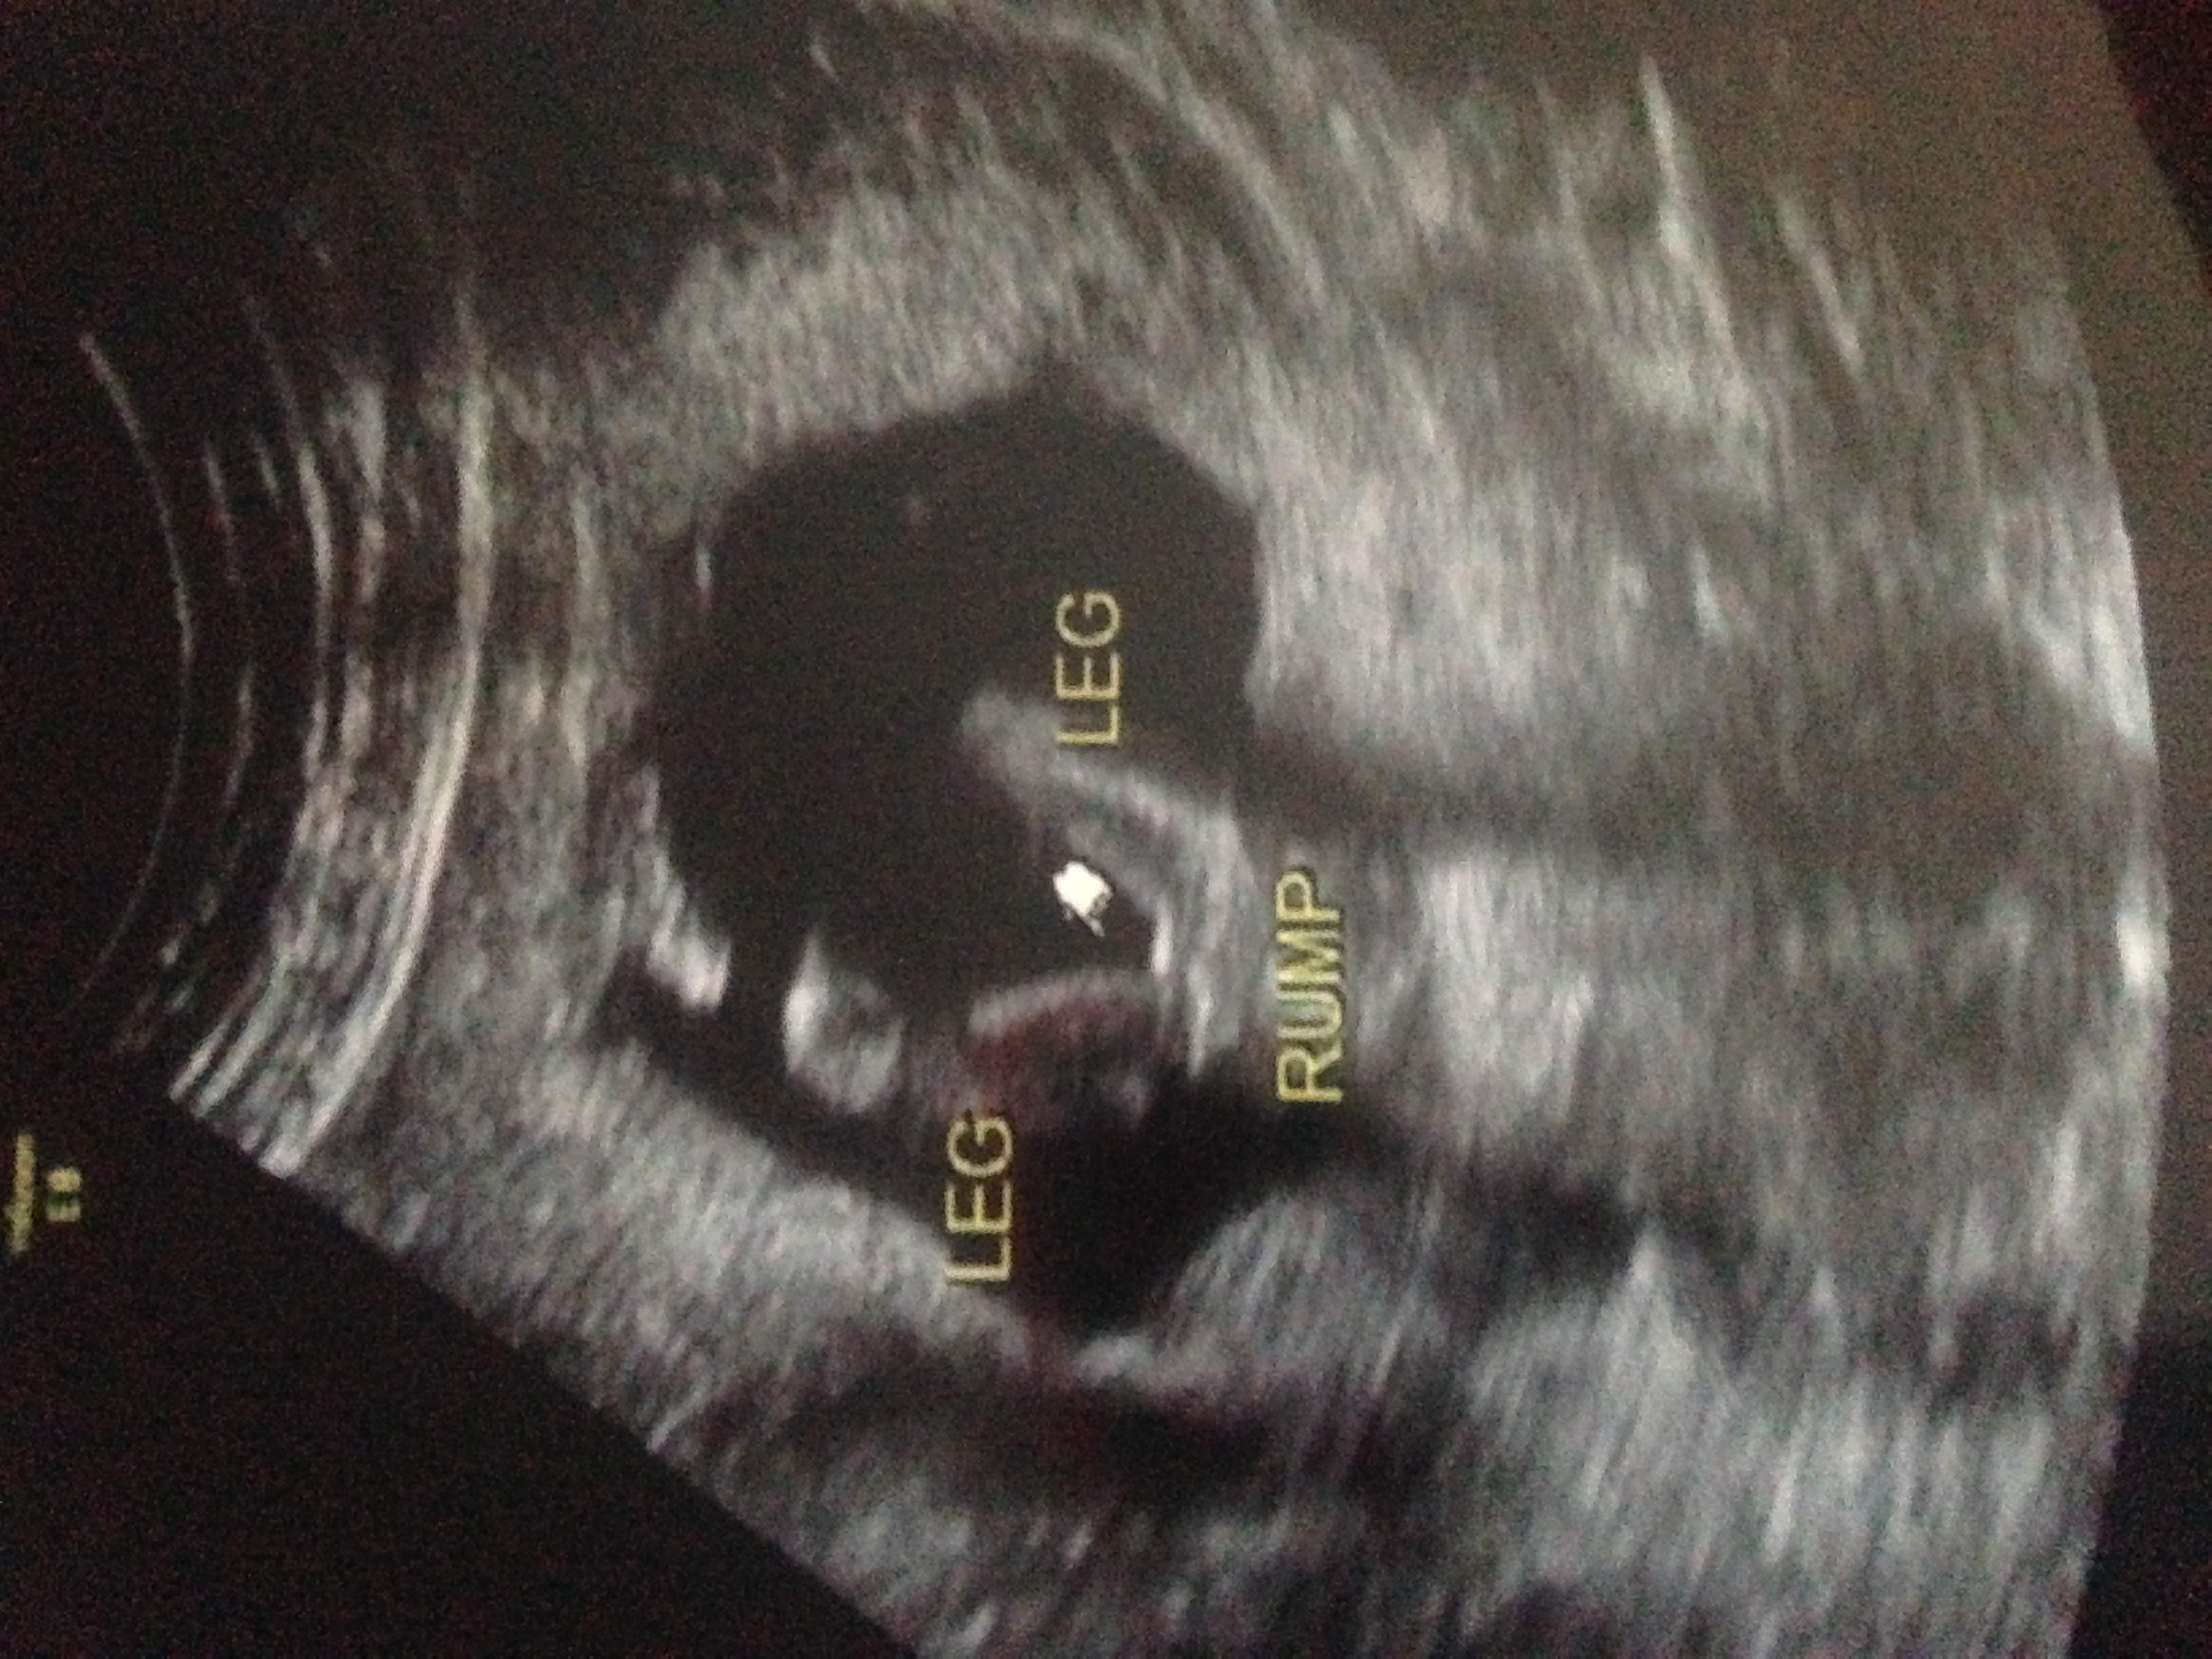

Just had an ultrasound. We could only see the parts of baby from behind. I'm 15 weeks and 4 days, no chance of a boy huh? This will be our 4th girl.

Doesn't look very boyish at this stage

There are no visible boy signs, but there is a chance they weren't captured at that shot. I would wait for the next u/s....